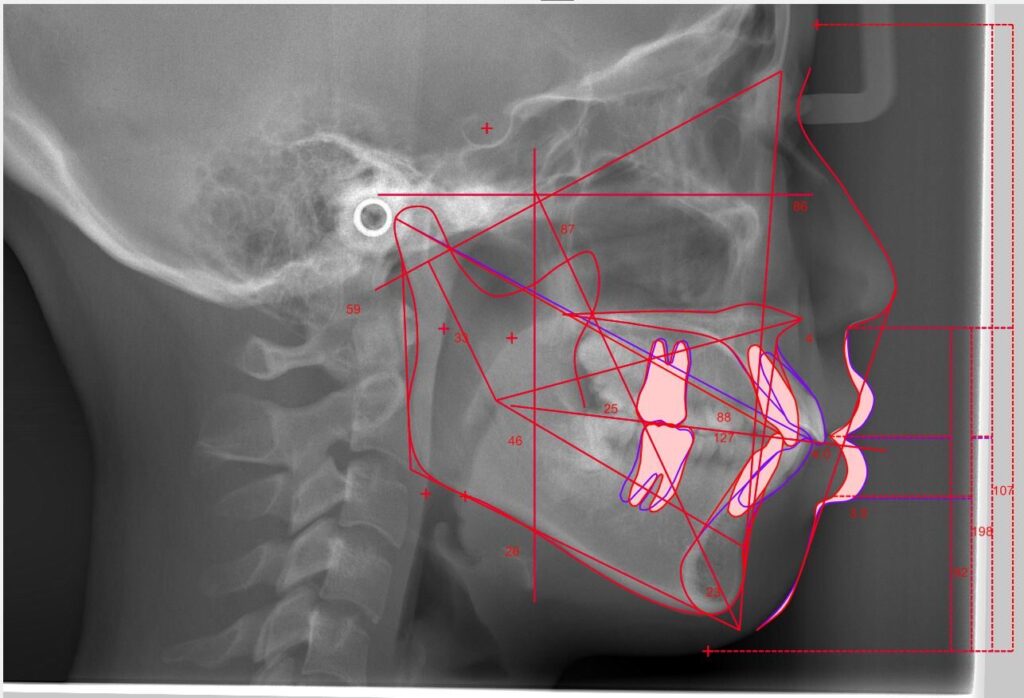

ただし、抜歯あるいは非抜歯による矯正歯科治療の適用の判断においては、頭部エックス線規格写真(セファログラム)などの精密検査を行うことが大切です。

抜歯あるいは非抜歯による矯正歯科治療の適用は、頭部エックス線規格写真と口腔模型などを用い

てアーチレングスディスクレパンシーや、軟組織の形態を客観的に評価し、かつ口唇閉鎖不全などの

軟組織の状態、治療期間、抜歯の負担など、多角的に考慮して決定される。